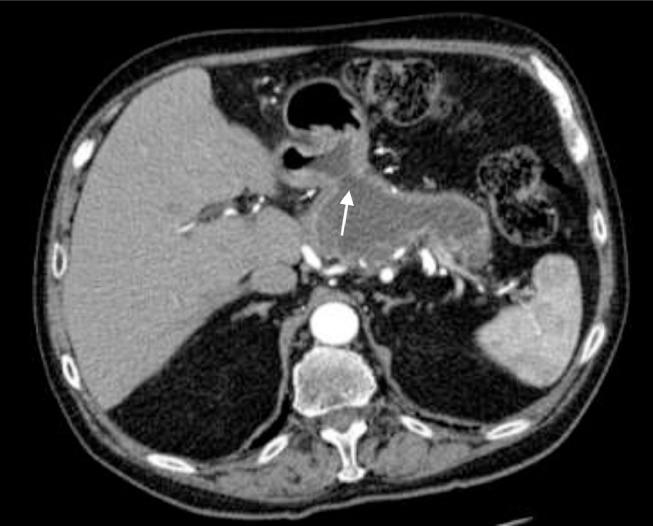

Intraductal papillary mucinous neoplasm complicated by a gastropancreatic fistula.

One of the rare complications of low-grade pancreatic neoplasms is fistulization into nearby structures. This often does not present clinically, but is incidentally identified in patients who have been imaged serially to monitor the progression of the disease. In this report, we present an uncommon complication of an intraductal papillary mucinous neoplasm, which developed a spontaneous gastropancreatic fistula in a patient who was conservatively managed. The clinical course, imaging features, and management of this case are discussed.